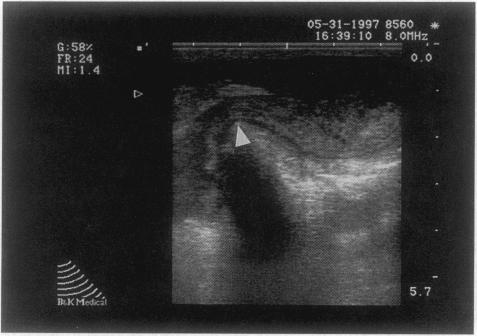

General surgeons perform US examinations of the thyroid gland, breast, gastrointestinal tract, peritoneal cavity (laparoscopy), and vascular system. Essentials of these examinations are discussed and a plan for educating surgical residents in US is outlined.

Focused assessment for the sonographic examination of the trauma patient, or FAST, is replacing central venous pressure measurements to detect hemopericardium and diagnostic peritoneal lavage to detect hemoperitoneum. Bedside US can be used to detect a pleural effusion so well in critically ill patients that lateral decubitus x-rays are rarely needed. US-directed biopsy of breast lesions is a common office procedure. Laparoscopic US allows tumor staging without formal celiotomy, and many hepatic and pancreatic surgical procedures include US as an adjunct. Endoscopic and endorectal US have added a new dimension to the assessment of many gastrointestinal lesions. Color flow duplex imaging and endoluminal US have significantly expanded the diagnostic and therapeutic aspects of vascular imaging. The training program developed at Emory University and Grady Memorial Hospital is offered as a model for educating surgical residents in US techniques.